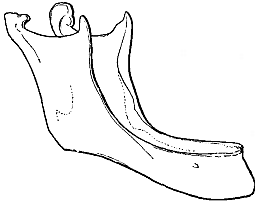

Ein gebücktes Mütterchen ist uns das Abbild des Alters. Ein gerunzeltes, zahnloses Mütterchen. Das Fettgewebe, das die Haut einst prall erhalten, ist geschwunden, und in Falten legt sich die Haut. Die bindegewebigen Bänder, die die Knochen der Wirbelsäule fest aneinander gebunden hatten, haben ihre Elastizität eingebüßt wie ein viel gebrauchtes Gummiband. Und die Wirbelsäule gibt dem Druck des Oberkörpers nach, der Oberkörper sinkt nach vorne. (Abb. 13). In den Kiefern schwindet der Teil, in dem einmal die Zähne gesessen, und die Zähne fallen aus (Abb. 14 u. 15).

|  |

| Abb. 14. Unterkiefer eines erwachsenen Menschen. Nach Toldt. | Abb. 15. Unterkiefer eines alten Menschen. Nach Ribbert. |